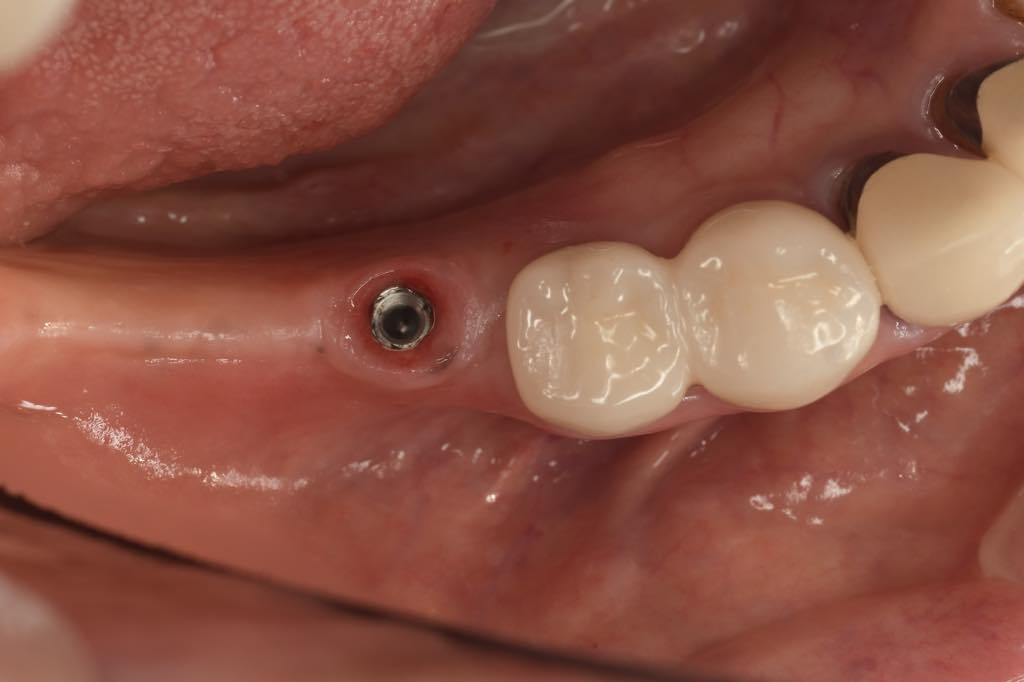

CASE 02

| 主訴 | 右下奥歯が欲しい |

| 治療内容 | 右下6番 インプラント治療 |

| 治療回数 | 8回 |

| 治療費用 | ¥390,000 |

| 想定される副作用 | 腫れ、痛み |